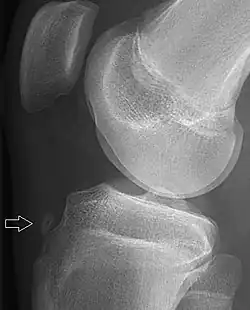

X-ray of a 15-year-old male, showing an older avulsion fracture of the tibial tuberosity.

A tibial tuberosity avulsion fracture is an incomplete or complete separation of the tibial tuberosity from the tibia. This occurs as a result of a violent contraction of the quadriceps muscles, most often as a result of a high-power jump. Incomplete fractures are usually treatable with the traditional RICE (rest, ice, compression, elevation) method, but complete/displaced fractures will most often require surgery to pin the tuberosity back in place. Tibial tuberosity avulsions occur most often in teenagers that engage in a large amount of sporting activities, and many studies have shown a history with Osgood-Schlatter's disease to be linked to the fracture.